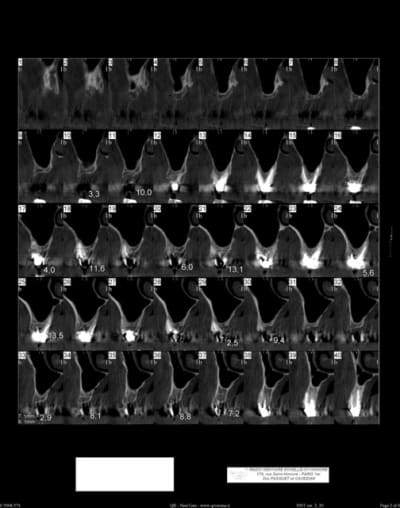

Bonjour, je sèche sur un cas, dont je vous joint le scan.

Malheureusement, j'ai peu d'épaisseur osseuse en antérieur; j'ai par ailleurs peu d'expérience en greffe ou expansion : je n'en connais pas les limites et ne sais donc pas comment aborder mon cas...

Faut voir l'expert de l'expansion xbK mais je pense que l'espace intercortical apical est trop faible; Je gérerai par une greffe d'apposition bloc osseux fixé en premier.

+1 pour la greffe...en plus j'ai l'impression d'un manque en hauteur également...

Sur la 1ere planche, il y a qq reconstitutions pano des antérieures.

Quant à la mandibule, elle est complètement dentée.

Ce qui me gène, c'est la finesse de l'os dans certaines zone ou y'a guerre plus de 2,5 mm et j'imagine mal ouvrir ça sans risquer de tout fracturer.